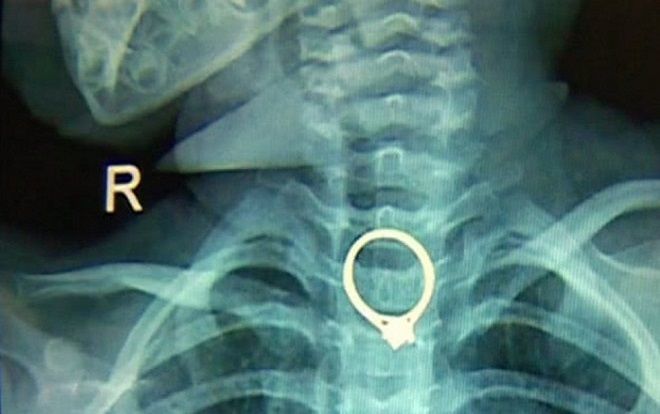

Mẹ tá hỏa phát hiện nhẫn kim cương chui vào họng con gái lúc nào không hay